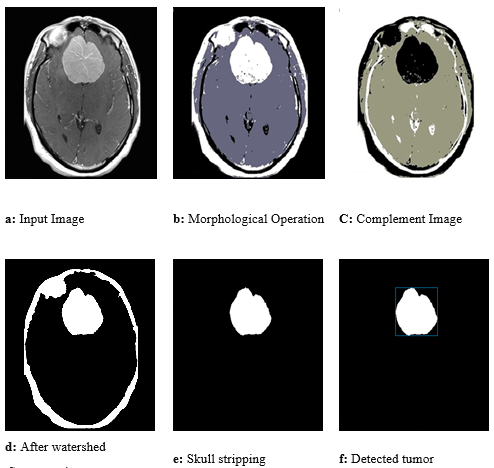

Calculate the regional minimum

By complement the image the calculation of the minimum value for any tumor which represents the center for each complete tumor image can be detected. The whole image of the tumor can be expressed as complete graph of lake catchment basins with a minimum value surrounded by two parallel dams (Figure 1).

Watershed segmentation

The idea of watersheds depends on envisioning a image in 3D: two spatial coordinates against dark levels [7,8]. In such a topographic understanding, we think about three sorts of focuses: a) points having a place toward regional minimum, b) point when water drops and c) point when water would probably fall. For a specific provincial least, the arrangement of focuses fulfilling condition (b) is called catchment basin or watershed of that base. A watershed locale or catchment bowl is characterized as the area over which all focuses stream “downhill” to a typical point. The focuses fulfilling condition (c) are named divide lines or watershed lines. The watershed transformation can be developed by flooding process on a dark tone picture and might be appeared as appeared in Figure 2.

Figure 2: Sample of tumor segmentation.

As watershed division method isolates any picture as various force parcels and furthermore the tumor cells have high proteinaceous liquid (fluid) which has high thickness and consequently high intensity, in this manner watershed division is the best tool to characterize tumors and high power tissues of brain.

Skull stripping

There are a severable methods accessible to perform skull stripping, the calculation utilized as a part of our proposed framework depends on an edge task and is portrayed in the accompanying advances:

a. Labeled Im = convert image that resulted from last phase into labeled image.

b. Find the region properties for Labeled Im.

c. Skull Reg = region that have maximum perimeter.

d. Skull Reg assigns 0 and other pixels assign 1